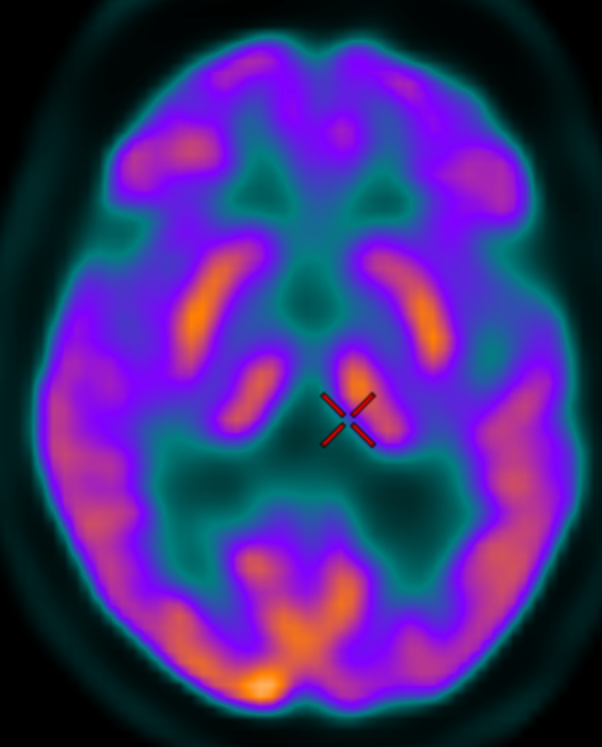

DAT imaging for Parkinsonsim